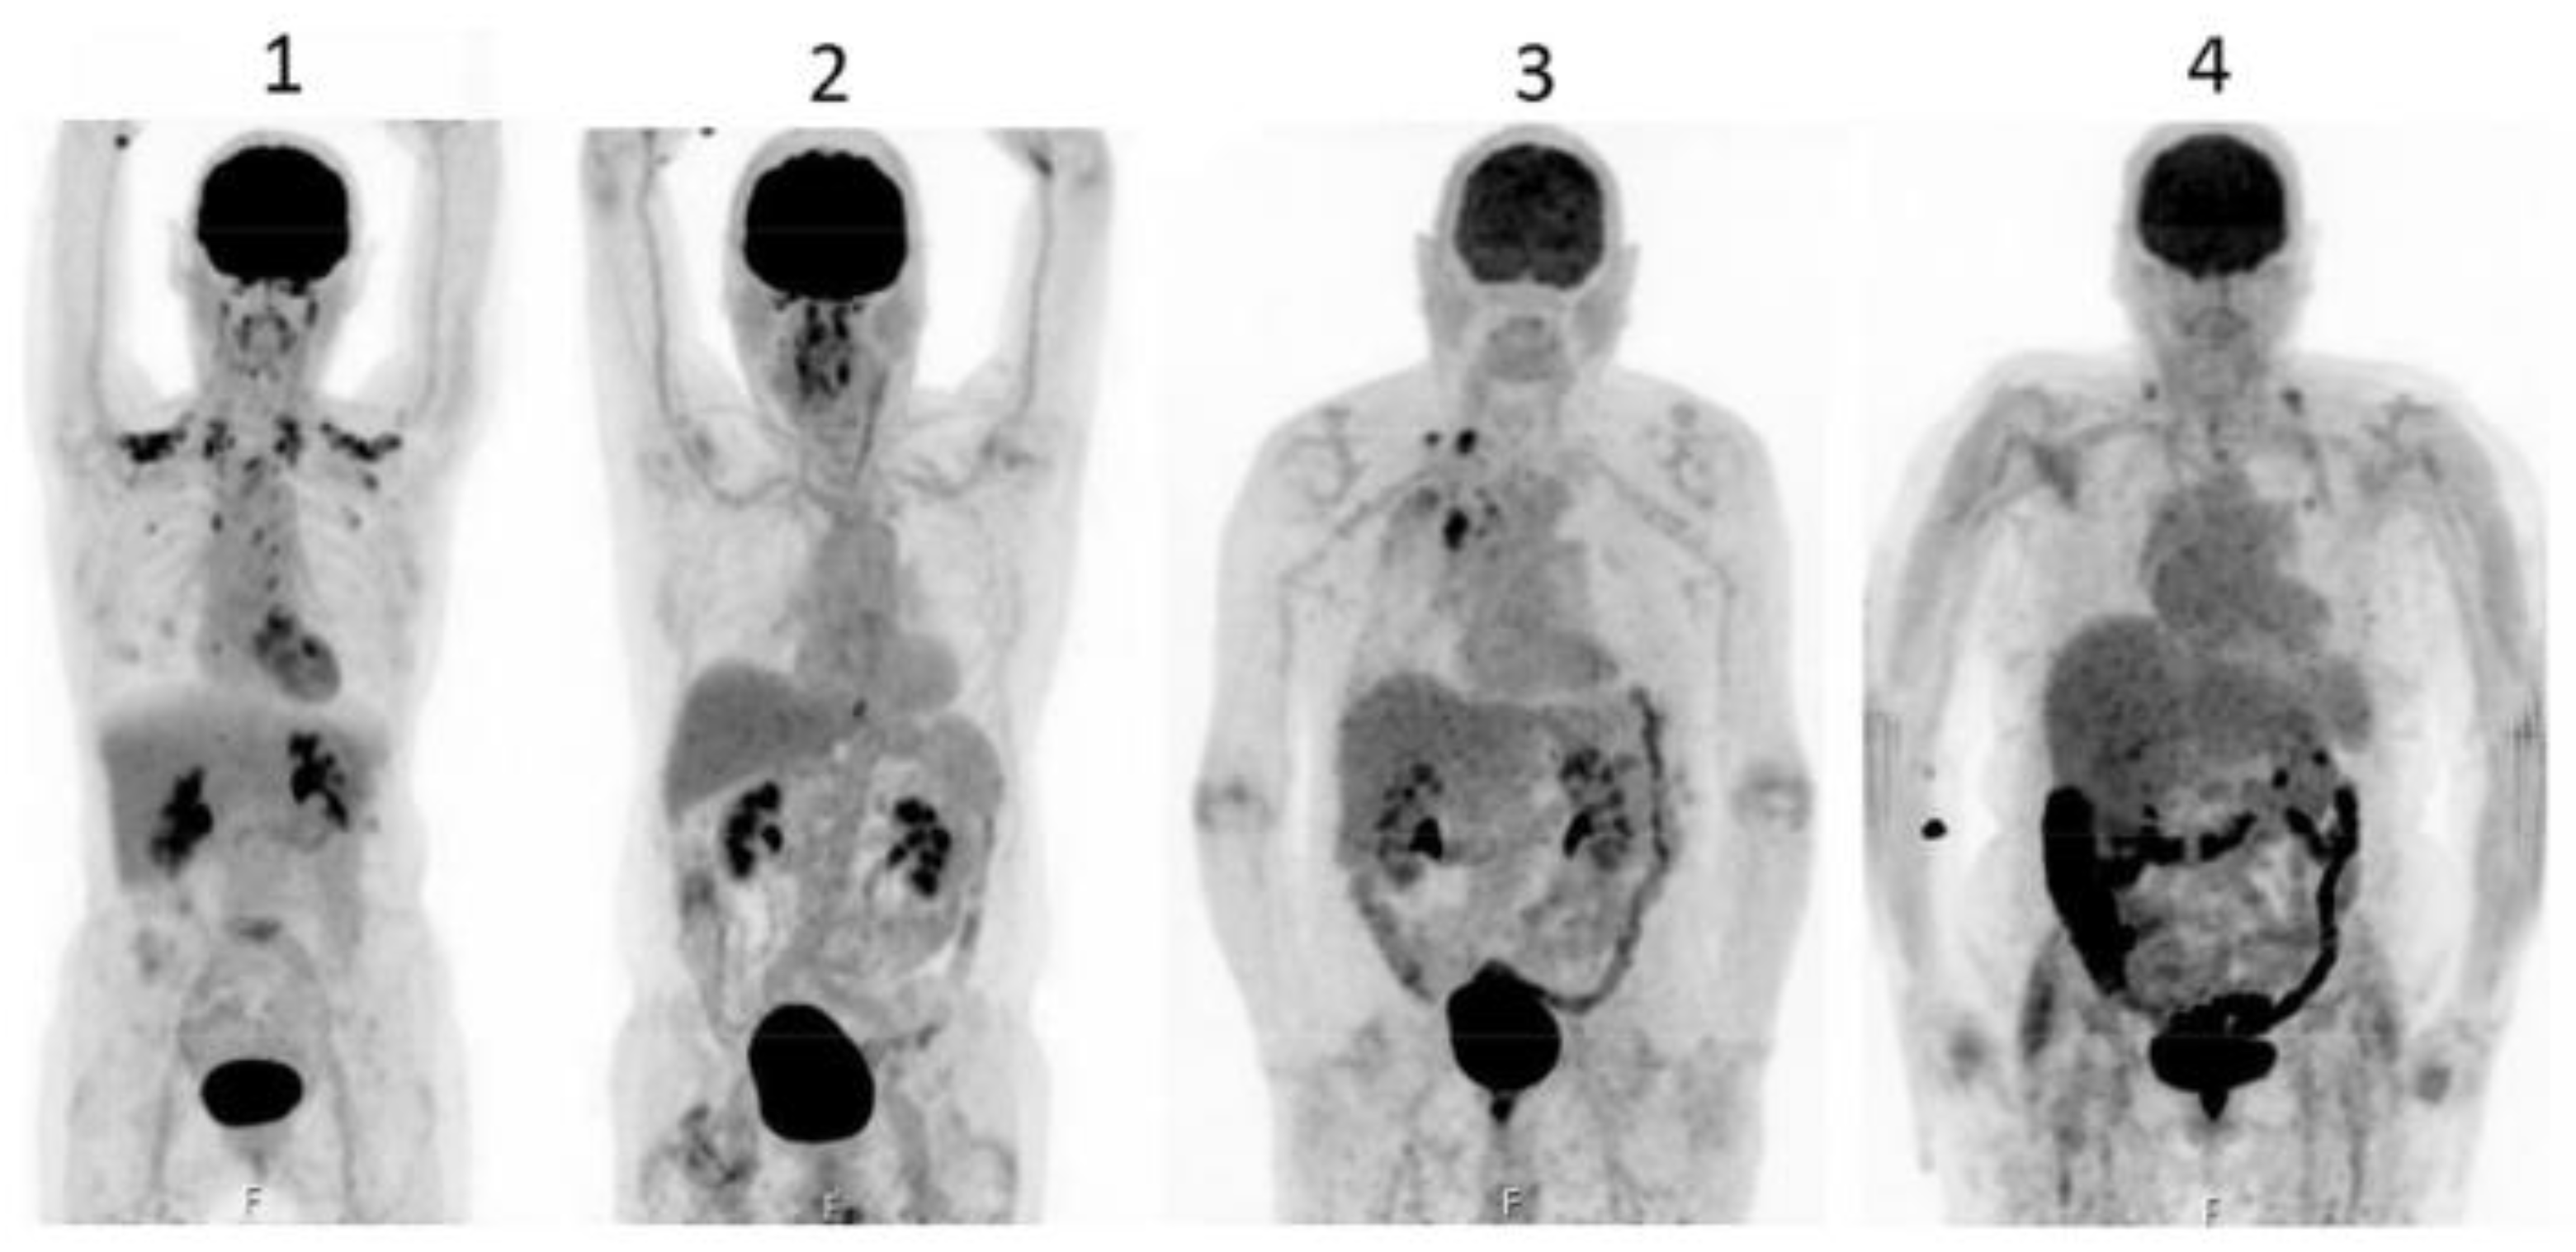

- Gontier E, Fourme E, Wartski M, Blondet C Bonardel G, Le Stanc E, Mantzarides M, Foehrenbach H, Pecking A-P, Alberini J-L.High and typical F18-FDG bowel uptake in patients treated with metformin.Eur J Med Mol Imaging 2008;35:95-99.

- Morita Y, Nogami M, Sakaguchi K, Okada Y, Hirota Y, Sugawara K, Tamori Y, Zeng F, Murokami T, Ogawa W.:Enhanced Release of Glucose Into Intraluminal Space of the Intestine Associated With Metformin Treatment as Revealed by [18F]Fluorodeoxyglucose PET-MRI.Diabetes Care 2020;43:1796-1802. [CrossRef]

- Özülkur T, Özülkur F, Mert M, Özpacaci T.Clearance of high intestinal F18-FDG uptake associated with metformin after stopping the drug.Eur J Nucl Med Mol Imaging 2010;37:1011-1017.

- Schreuder N, Klarenbeek H, Vendel BN, Jager PL, Kosterink JGW, van Puijenbroek EP.Discontinuation of metformin to prevent metformin-induced high colonic FDG uptake:is 48 h sufficient?.Annals of Neclear Medicine 2020;34:833-839.

- Massollo M, Marini C, Brignone M, Emionite B, Salani BRiondato M, Capitano S, Fitz F, Democrito A, Amaro A, Morbelli S, Piana MMaggi D, Cilli MPfeffer U, Sambuceti G.Metformin Temporal and Localized Effects on Gut Glucose Metabolism Assessed Using F18-DG PET in Mice.J Nucl Med 2013;54:259-266.

- Tu DG, Chen C-R, Wang Y-W, Tu C-W, Huang YC.Bowel-cleansing methods affecting PET-CT Image interpretation.Nucl Med Commun 2011;32:570-574.

- Chen Y-K, Chen J-H, Tsui C-C, Chou H-H, Cheng R-H, Chiu J-S.Use of Laxative-augmented Contrast Medium in the Evaluation of Colorectal Foci at FDG PET.Radiology 2011;259 (2):525-533.

- Katsumata R, Manabe N, Ayaki M, Tanikawa T, Fujita M, Ono Y, Fujiwara H, Suehiro M, Monobe Y, Kato K, Kawamoto H, Haruma K.Increased Colonic Fluorodeoxyglucose Uptake in Melanosis Coli-A Case Series of Three Patients.Gastro Hep Advances 2022;1:125-128.